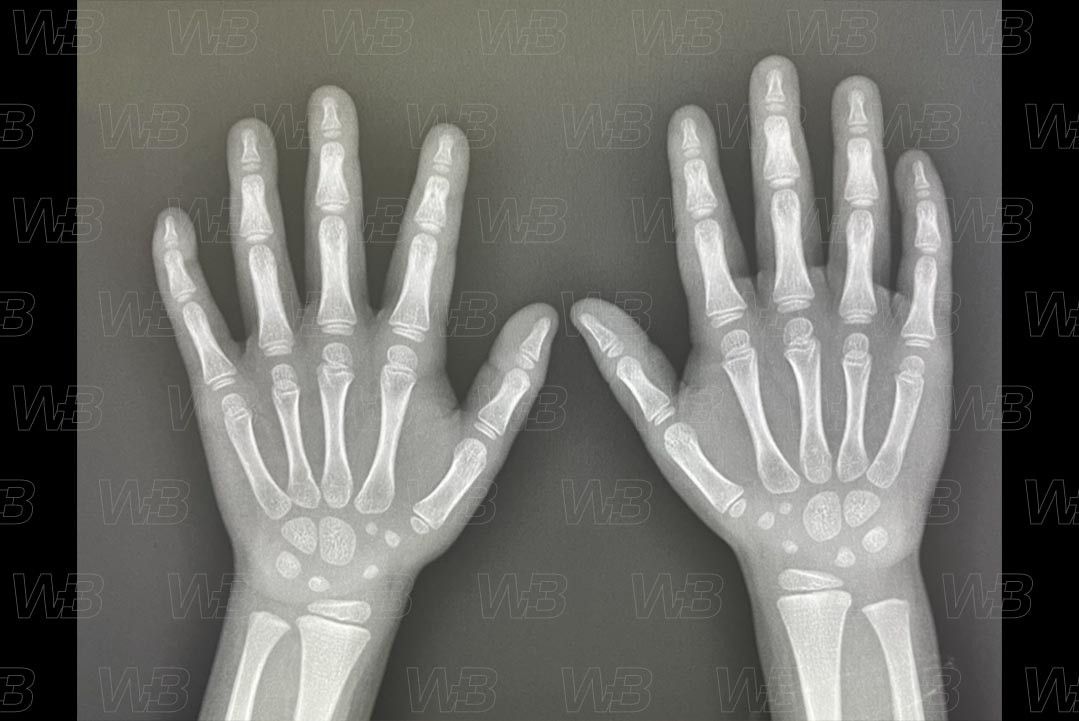

Atlas idade óssea - Feminino - 4 anos e 2 meses

RADIOGRAFIA MÃOS E PUNHOS (IDADE ÓSSEA)

Feminino

4 anos e 2 meses:

• Trapezoide e escafoide.